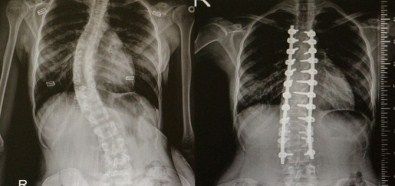

Omurga Eğriliği Olanlar OMÜ'de Şifa Buluyor

Skolyoz(omurga eğriliği) olan hastalar Ondokuz Mayıs Üniversitesi(OMÜ) Tıp Fakültesi’nde şifa buluyor.

Skolyozun özellikle kız çocuklarda daha sık görülen bir durum olduğunu söyleyen Yrd. Doç. Dr. Mesut Kılıç, "Skolyoz hastalığı özellikle çocuklarda ve gençlerde gerek kozmetik gerekse fonksiyonel açıdan şikayetlere sebep oluyor. Tedavide çoğunlukla cerrahi dışı yöntemler uygulanır. Korse, egzersiz gibi. Fakat bazı hastalarda cerrahi tedavi gerektirmektedir. Cerrahide günümüzde modern teknikler kullanılmaktadır. Halk arasında platin diye bilinen uygulamalarla düzeltme sağlanmaktadır. Ayrıca son dönemlerde teknolojik gelişmelerle ortaya çıkan nöromonitörizasyon dediğimiz bir sistem uygulanıyor. Hasta uyutularak bilgisayara bağlanıyor. Ameliyat sırasında bir felç durumu var mı yok mu? Sinir yapılarında bir zedelenme var mı yok mu bunu bize bildiriyor. Halk arasında bu tür ameliyatlarda ’felç olursunuz’ korkusunu biz çok duyuyoruz. Fakat bu uygulama ile felç riskini yüzde sıfıra yakın indiriyoruz" dedi.